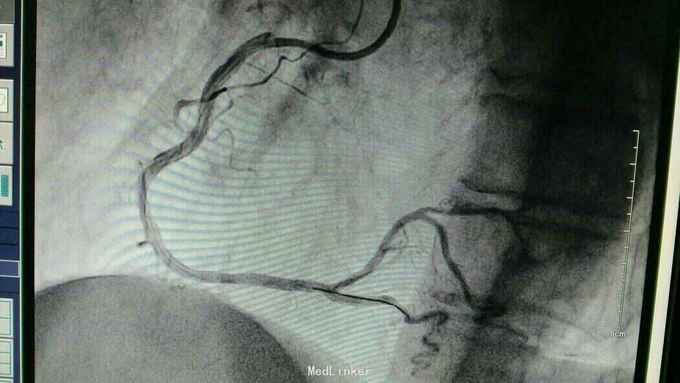

急性下壁心肌梗死,立即启动绿色通道,行急诊冠脉造影明确冠脉病变,必要时PCI治疗,行CAG示:LAD中重度狭窄,LCX尚可,RCA中段局限重度,可见前向血流,选段后降支处重度狭窄,血管钙化明显。考虑此次靶血管为RCA中段处,血管钙化迂曲明显,拟处理RCA,术中导丝到达远端后,预扩球囊反复高压扩张后,支架均无法通过,采用双导丝增加支撑依然无法通过,再更换高压后扩球囊高压扩张,锚定等,最终成功植入支架

急性心梗有时候处理相对较容易,但此病变在于血管钙化迂曲明显,且再次详细阅片后发现局部有“礁石”样病变,预扩球囊及后扩球囊不易扩张,有时需切割或旋磨,但对于急性心梗,如果血流达到理想级别,可不勉强处理,急性心梗中,有些病变为固定狭窄基础上急性血管闭塞,处理并非如一般血栓病变那样容易,造影后仍然需要详细阅片,根据具体病变情况选择合适手术处理方法